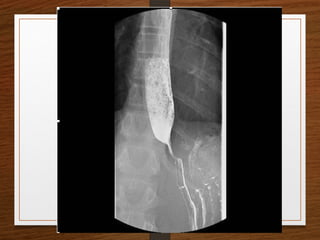

Contrast X-rays

• Barium Swallow

• Achalasia

• Ca Esophagus

• Barium Meal

• GOO

• Barium Enema

• Ca Colon

• IVP

Contrast Films

Barium Studies

Barium studies can demonstrate GI abnormalities in three ways

1. Mucosal relief views of the collapsed or partially collapsed

lumen obtained with a small volume of barium.

• particularly useful for showing abnormalities involving the

submucosa, such as esophageal varices.

2. Single-contrast views of the filled lumen obtained with a

large volume of low-density barium

• These views enable visualization of contour abnormalities,

strictures, and large polypoid defects.

3. Double-contrast views obtained after the mucosal surface

has been coated with a thin layer of high-density barium

and the lumen has been distended with gas

• These views enable visualization of subtle mucosal lesions, such as

the early changes of inflammatory bowel disease and early

neoplastic lesions

• Barium suspensions for single-contrast studies

should be of moderate density (50%-100% w/v)

when not diluted.

• For the double-contrast examination, we use high-

density 250% w/v barium

Barium Studies Barium studiescan demonstrate GI abnormalities in three ways 1. Mucosal relief views of the collapsed or partially collapsed lumen obtained with a small volume of barium. • particularly useful for showing abnormalities involving the submucosa, such as esophageal varices. 2. Single-contrast views of the filled lumen obtained with a large volume of low-density barium • These views enable visualization of contour abnormalities, strictures, and large polypoid defects. 3. Double-contrast views obtained after the mucosal surface has been coated with a thin layer of high-density barium and the lumen has been distended with gas • These views enable visualization of subtle mucosal lesions, such as the early changes of inflammatory bowel disease and early neoplastic lesions

• Barium suspensionsfor single-contrast studies should be of moderate density (50%-100% w/v) when not diluted. • For the double-contrast examination, we use high- density 250% w/v barium